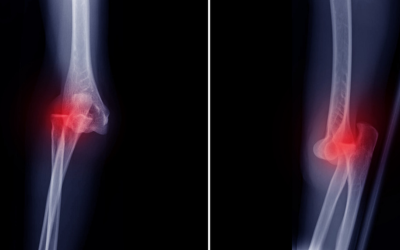

Luxación Traumática: La lesión de rodilla más grave (y por qué no debes entrar en pánico)

Al hablar de lesiones articulares, solemos pensar en desgarros de menisco o esguinces. Sin embargo, existe una condición sumamente grave, aunque poco común: la luxación traumática de rodilla. Si experimentas un dolor fuerte y estás buscando un traumatólogo cerca de...